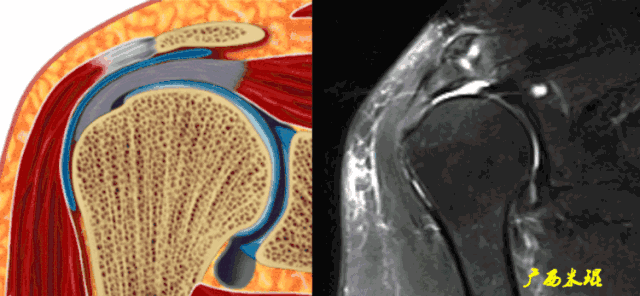

(2)斜矢状位:垂直于冈上肌长轴,观察肩峰形态及喙肩弓,观察肩袖4个组分的短轴断面。

(3)平行于关节盂/垂直于盂肱关节,主要评估盂唇,同时兼顾肩胛下肌、冈下肌及小圆肌。

正常肩袖的MRI表现

各个序列肩袖均表现为均匀的低信号,是肌腱的延续。